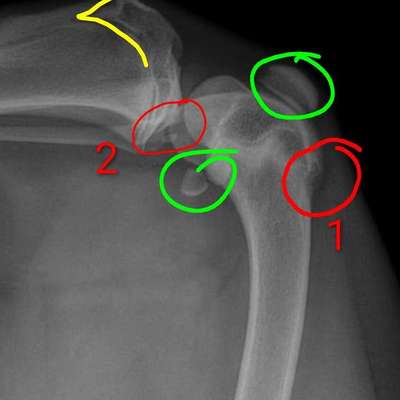

Vorab: die Qualität des Bildes hier auf dem Handy reicht nicht für eine valide Beurteilung. Röntgenbilder werden an speziellen Monitoren beurteilt und das nicht ohne Grund.

Was sehen wir?

In Grün eingekreist die beiden Sesambeine. Oben die Patella und unten die beiden Sesambeine vom M. gastrocnemi (Kniekehlmuskel). Die gehören beide da hin.

In Gelb die Wachstumsfuge des Schienbeins.

In Rot ist 1. das, was ich für die Knochenhautentzündung halten würde am Oberschenkel.

Rot 2 könnte man tatsächlich als Gelenk-Chip interpretieren, allerdings ist die Aufnahme etwas verkippt, das mag also auch an der Überlagerung liegen.

Oben wo der Kringel ist. Da ist der Knochen aufgetrieben. Ist ja eine andere Röntgenperspektive und anderes Gelenk.